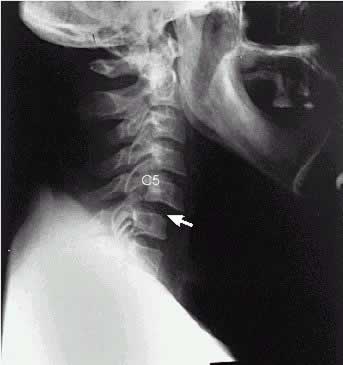

S13.1 Вывих шейного позвонка

Подвывих шейного позвонка С5